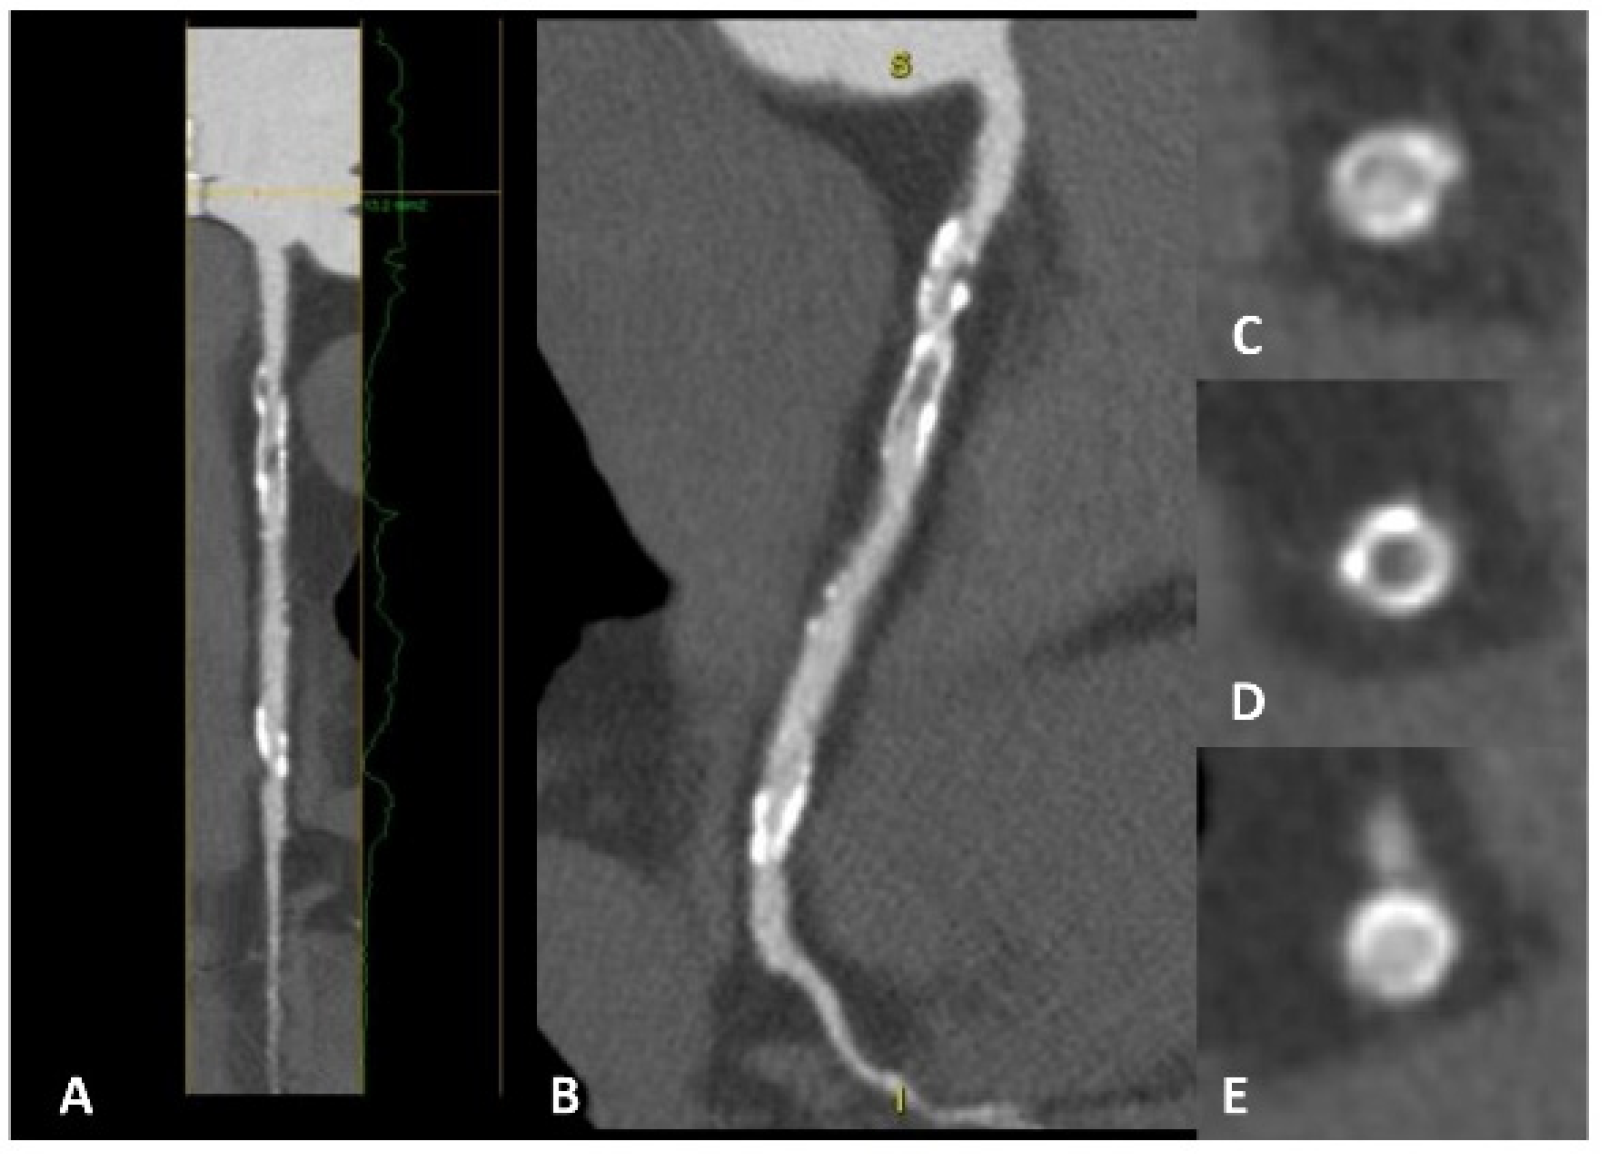

Figure 5.

A patient with previous percutaneous revascularization of the right coronary artery, with cardiac CT showing evident in-stent restenosis in both long-axis view (panels A,B) and short-axis view (panels C–E). In panel (D), a clear hypodensity is evident inside the stent lumen compared with panels (C,E).